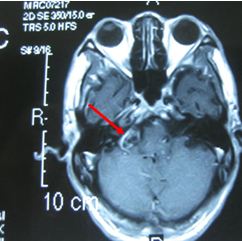

Trường hợp 1: Bệnh nhân Lê Văn C, nam, 71 tuổi. Được chẩn đoán là u dây thần kinh số VIII với triệu chứng ban đầu là đau đầu, ù tai. Bệnh nhân có tiền sử bệnh tim nên không còn chỉ định phẫu thuật mổ mở. Bệnh nhân được xạ phẫu bằng dao gamma quay với liều 14Gy. Sau xạ phẫu 6 tháng, về lâm sàng: hết đau đầu và ù tai, không có triệu chứng liệt mặt.

Trước điều trị:  u dây VIII bên phải có kích thước 2cm

Sau xạ phẫu 6 tháng: u nhỏ hơn về kích thước và có hoại tử trong u

Hình 2. Hình ảnh MRI u dây thần kinh số VIII trước và sau xạ phẫu bằng dao gamma quay